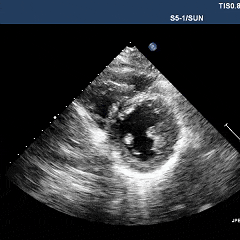

超声心动图显示,在左心室中侧壁邻近前乳头肌处,有一大小约27.5×16.5mm的中等回声团块,与邻近结构分界不清(图1A、1B,动图1、2)。通过胸骨旁长轴、改良胸骨旁短轴及心尖四腔心切面进行彩色多普勒检查,未探测到明确的瘤内血流信号,考虑血流信号的缺失很可能源于声学局限性。

动图1、2